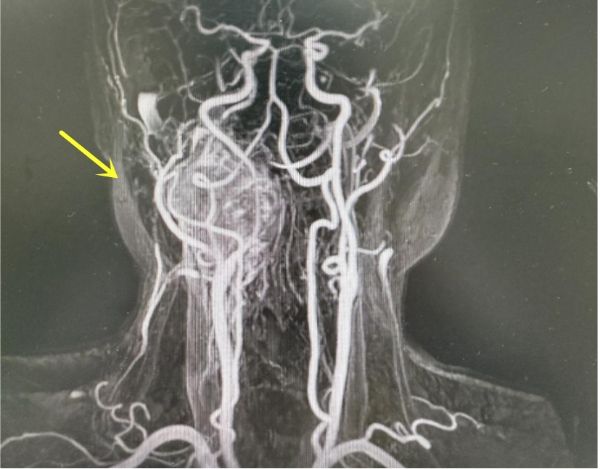

患者术前MRA影像表现 箭头示巨大颈动脉体瘤

患者张先生(化名)今年49岁,因“头痛1年余,加重伴咽部异物感3月”入院。经检查,张先生颈部有一个约6cm×5cm的巨大肿块,初步诊断为颈动脉体瘤。更令人担忧的是,PET-CT显示肿瘤从颈动脉分叉处向上延伸至颅内,并且肿瘤紧贴着颈动脉、迷走神经等重要结构,颈内动脉狭窄程度大于70%,葡萄糖代谢增高,考虑恶性肿瘤。颈动脉体瘤是一种罕见的副神经节瘤,位于颈动脉分叉处,因肿瘤血供丰富且与颈部大血管、神经紧密相邻,手术风险极高,稍有不慎可能引发大出血、脑缺血或神经功能损伤。国内文献报告类似大小的颈动脉体瘤仅有1例,类似切除手术颅神经的损伤几率高达50%,偏瘫率高达30%。但是如果不进行治疗,肿瘤就像一颗“定时炸弹”,随时可能破裂出血,患者生命危在旦夕。